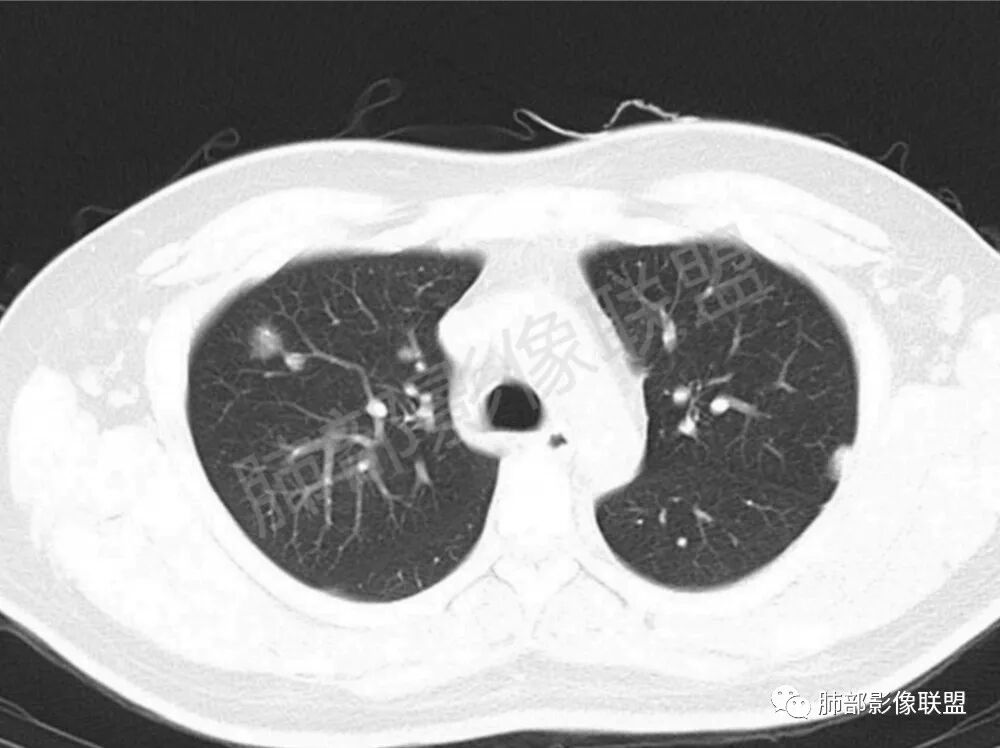

男性,22岁,HIV病史,症状半年,双肺多发大小不等结节影,边缘光滑,密度均匀,以胸膜下分布为主,部分与胸膜相连,胸膜下脂肪间隙可见,病灶近段支气管走行病灶内,远端似有堵塞,无增强图像,考虑隐球菌,鉴别:淋巴瘤,GPA

双肺多发结节影,膨隆,边缘光滑,圆顿,沿支气管血管束分布为主,部分贴胸膜,部分见空洞,空气支气管征

两肺多发结节性,大部分位于胸膜下,部分结节周围可见晕征。局部结节内可见扩张的支气管,纵隔淋巴结大,脾大,22岁男,HIV阳性,常规先考虑隐球菌。鉴别淋巴瘤,结核,马儿。

男,22,半年前咳嗽伴少痰,查HIV阳性,痰查TB阳性,既往有肺部斑片影伴空洞、纵隔淋巴结肿大、脾大。SCC、CA50、CA199、FER增高,此次胸部CT:两肺多发结节影,部分沿血管束分布,部分贴胸膜下,大小不一,密度不一,部分较散、边缘模糊,部分较实、圆钝、周围模糊晕,部分结节有支气管进入穿行自然,部分结节有血管分支自如通过。考虑HI∨相关淋巴增殖类病变,淋巴瘤?LYG?鉴别PC、TB。

1.双肺多发大小不一结节,外围为主,边界尚清,部分周围似有GGO

2.类圆形,部分与胸膜相连,糊墙

3.支气管通畅或近端堵塞

影像学缺乏特征性,以支气管血管周围、胸膜下及双肺下叶周边多发结节影最多见,结节易坏死形成空洞,伴有游走性和多变性的特征,结节周围可有磨玻璃样晕征,有时也可见单发结节影、薄壁的囊状阴影或弥漫性浸润影。肺门、纵隔淋巴结肿大少见, 可见胸腔积液和气胸。